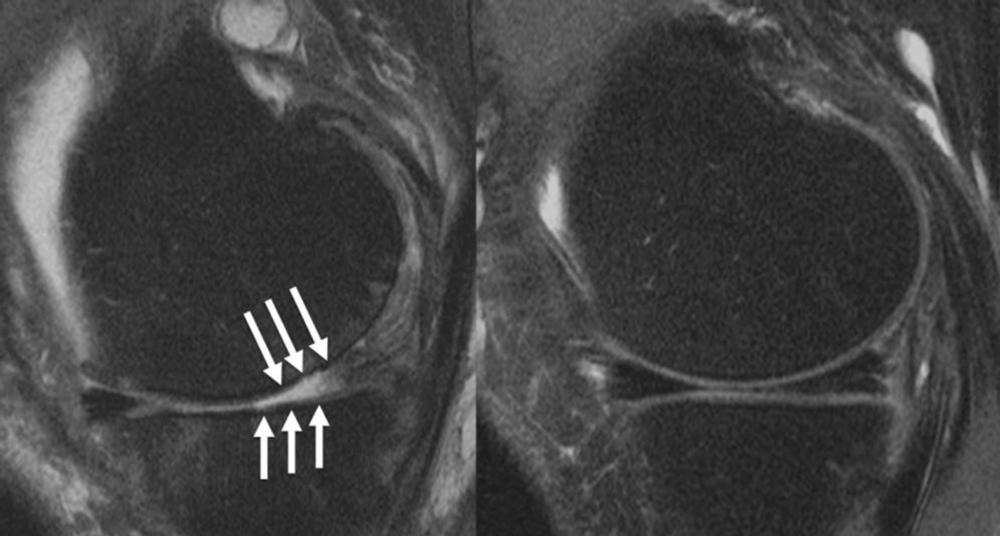

Figure 4. : Knee joint of a patient showing (A) severe cartilage defects and (B) intact knee joint.